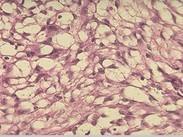

小腸平滑肌肉瘤是起源于小腸壁肌層、黏膜下肌層和腸壁血管平滑肌的惡性腫瘤,是小腸結(jié)締組織惡性腫瘤中最常見的一種。在小腸不滑肌瘤中,平滑肌肉瘤與平滑肌瘤之比為2~4∶1好發(fā)于空腸,其次為回腸和十二指腸。